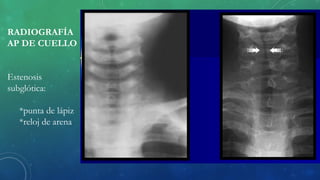

RADIOGRAFÍA

AP DE CUELLO

Estenosis

subglótica:

*punta de lápiz

*reloj de arena